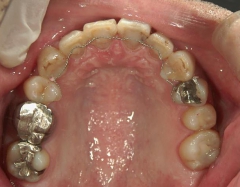

矯正歯科 治療前矯正歯科 治療前

矯正歯科 治療前 右上4番、左右下4番 計3本抜歯し、叢生を改善

no.22_8175_治療前_右.jpgno.22_8175_治療前_正面.jpgno.22_8175_治療前_左.jpg